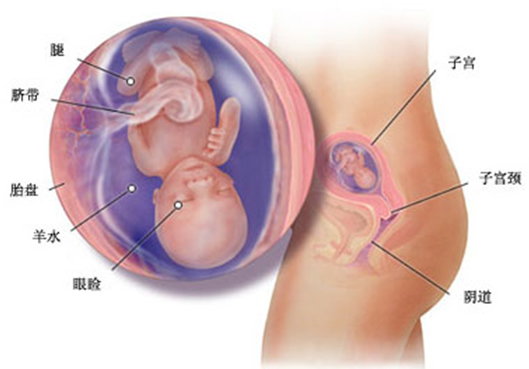

怀孕第 16 周胎儿发育情况

你可能还不知道,你子宫里的小居民现在开始打嗝了,这是胎儿呼吸的先兆。现在你还听不到任何声音,因为胎儿的气管充斥的不是空气,而是流动的液体。你现在的体重可能已经增加了 2000-4500 克,而胎儿的体重还只有 150 克,身长超过 12 厘米。

现在,胎儿腿的长度超过了胳膊,手指甲完整地形成了,指关节也开始运动。

现在胎儿的生殖器官已经形成,用 B 超可以分辨出胎儿的性别了,你一定想知道是男孩还是女孩,但一般来讲男孩和女孩各占一半,男孩略多些。一般情况下,国内的性别检查,只用于判断某些通过性别遗传的疾病检测。

拥有一个自己的宝宝,这个梦想原来似乎那么遥远,但现在你会感到近在咫尺,因为你就要真切地感到胎动了。在 16 周到 20 周之间,妈妈可以感到明显的胎动。如果你已经有过怀孕史,你会感到胎动的时间比以前提前了。现在胎动时你会有喝了饮料后胃肠蠕动的感觉,注意记录下第一次胎动的时间,下次去医院做检查时告诉医生。